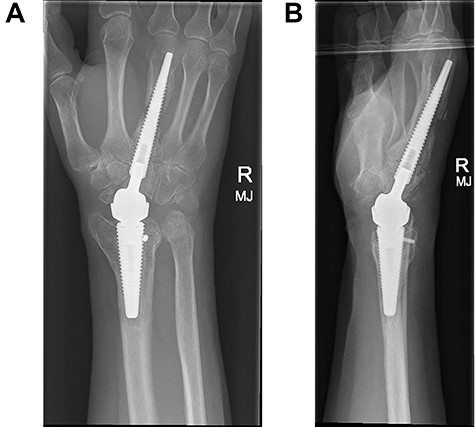

Following appropriate consultation and consent, she underwent total wrist arthroplasty. She reported complete pain relief and an improved range of movement. Ten weeks following surgery the patient presented in the emergency department following a fall. She landed heavily on the dorsiflexed hand and wrist, immediately noticing a change. Imaging confirmed that she had sustained a periprosthetic fracture in the middle finger metacarpal with dorsal displacement of the implant (Fig. 2A and B). Following a trial of non-operative treatment, she underwent revision surgery. The distal metacarpal implant was removed and replaced with a longer implant and the metacarpal fracture defect region was reinforced with autologous bone graft (Fig. 3A and B).

(A and B) PA and lateral radiographs following revision surgery to a longer metacarpal implant.

Three months following surgical treatment of her periprosthetic fracture, when reviewed in the outpatient clinic, the fracture had united and she demonstrated an excellent range of pain free motion and improved wrist function reflected in an improved PRWHE score from 66 preoperatively to 22, 3 months after surgery.

We recommend that the distal component should be positioned beyond the isthmus in the middle finger metacarpal to maximize the intramedullary fix, reduce any tendency to malalignment and any subsequent tendency towards dorsal migration of the implant. We would suggest that this is critical for success. We have found that it is easier and more likely that a short metacarpal implant will be implanted in unacceptable dorsal malalignment.

In this case, revision surgery with a longer metacarpal implant avoided the need for wrist fusion as a salvage procedure and it is now our routine practice to site the distal implant beyond the isthmus.